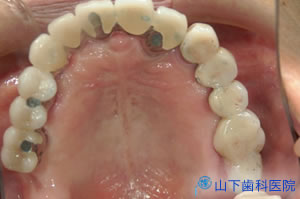

| 上顎の残っている歯すべてに金属製の内冠または沈下を抑える根面板を被せています。 | ![]() |

| 外冠が付いている「入れ歯」は味覚を落とさないよう、口蓋を中抜きした金属床です。 | ![]() |